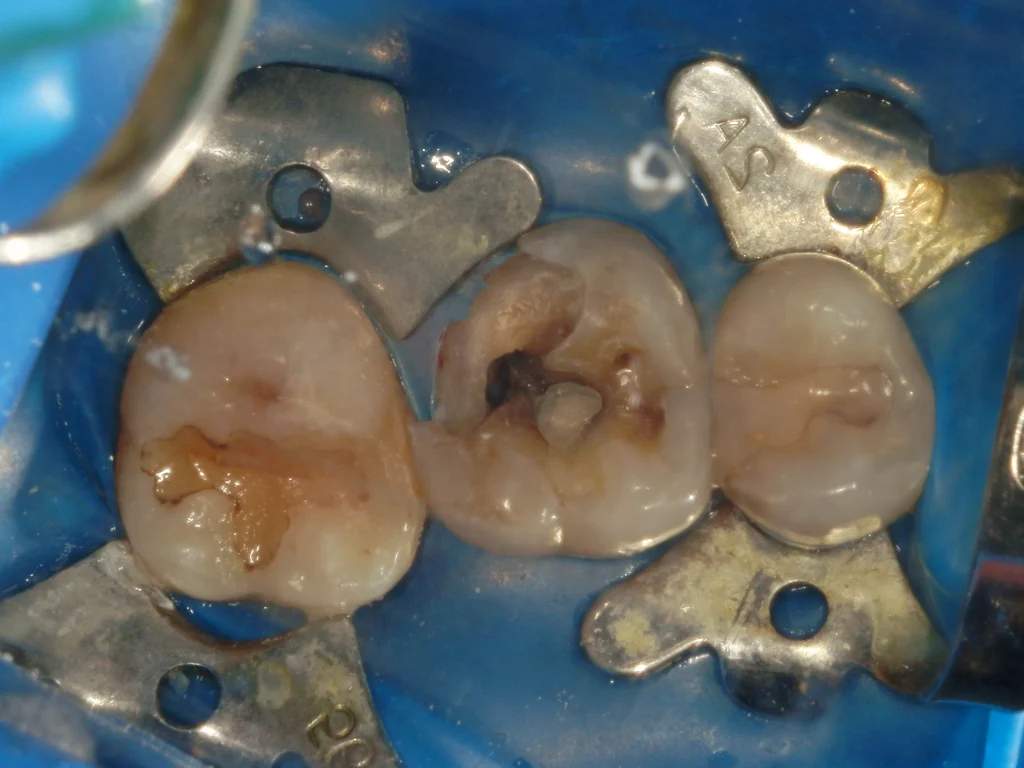

ラバーダム防湿を行い、丁寧に虫歯の除去を行う。

神経が出る位置まで虫歯が進んでいるため、一旦ここで虫歯除去を停止し壁を作っていきます。

そうすることで、さらに清潔な環境を揃えることができます。

虫歯除去を再開し、すぐに歯髄が露出し出血してきました。

止血と消毒を行い、MTAセメントを貼付していきます。